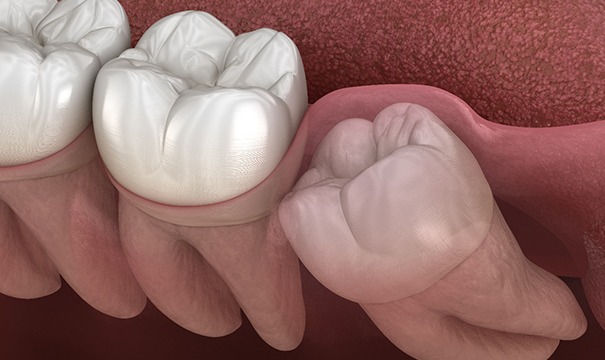

Because the wisdom teeth erupt later than the other teeth, there often isn’t enough room for them in the mouth. Consequently, they may become trapped beneath the gums, which can result in significant pain and swelling. Furthermore, because the wisdom teeth often come in at an angle, they may push against the other teeth, potentially damaging them or pushing them out of alignment. Finally, the location of the wisdom teeth can make them difficult to clean properly, increasing your risk for cavities and other oral health issues.

Wisdom teeth that have emerged from beneath the gums can sometimes be removed via a simple extraction. This involves using a dental elevator to loosen the teeth until they can be gently taken out of their sockets. However, if your wisdom teeth are trapped under your gums, a surgical approach may be required. An incision will need to be made in the gums so that the teeth can be accessed. Furthermore, it might be necessary to divide the teeth into sections that can be removed one at a time.